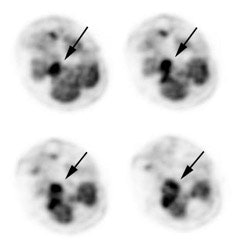

Large laryngeal cancer: The patient shown below had a large laryngeal cancer (white arrows). The PET exam demonstrated very prominent uptake within the mass, but no evidence of metastatic disease.

Large laryngeal cancer: The patient shown below had a large laryngeal cancer (white arrows). The PET exam demonstrated very prominent uptake within the mass, but no evidence of metastatic disease. |